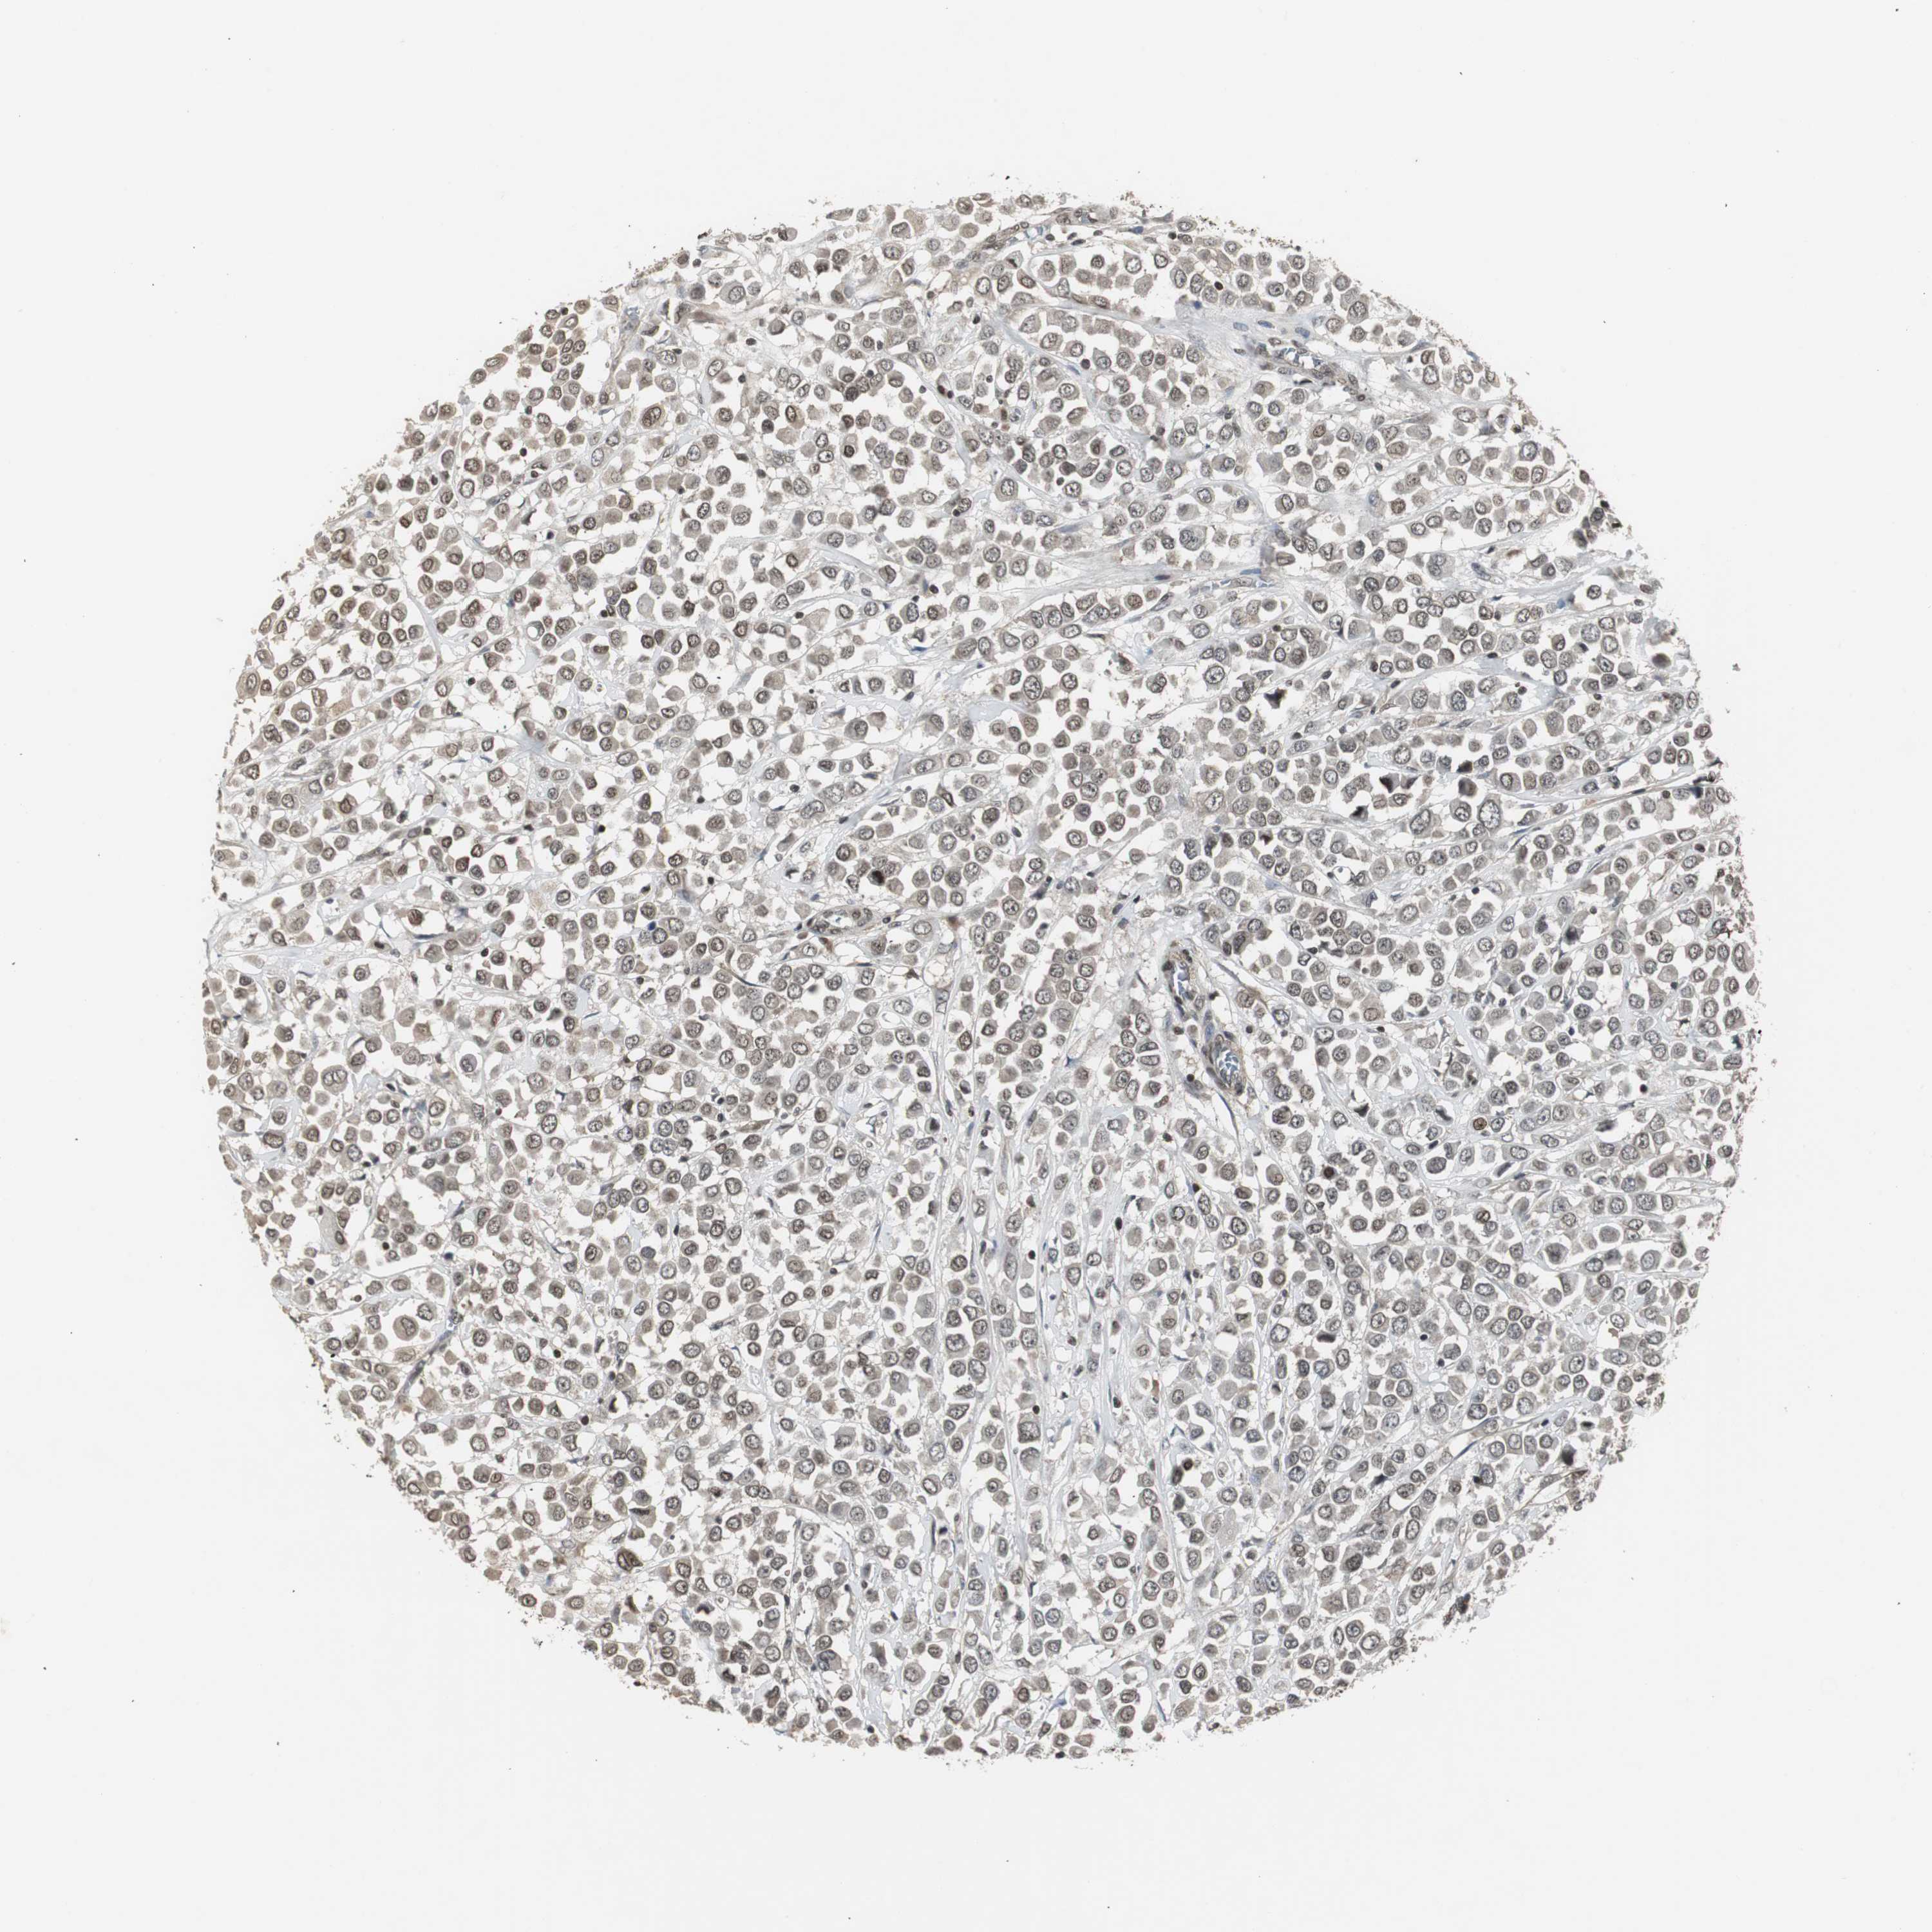

CANCER BREAST CANCER Show tissue menu

BRCA TCGA BRCA VALIDATION PROTEIN EXPRESSION